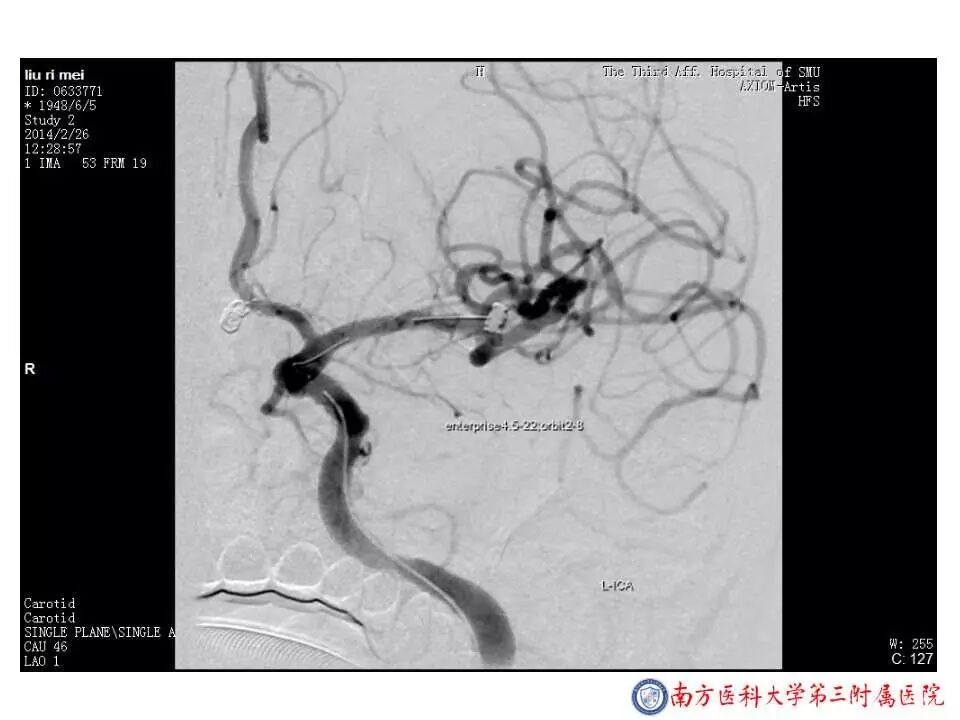

今天为大家分享的是“强生医疗CNV-神经介入专栏”第二十五期,由南方医科大学第三附属医院神经外科主任黄理金教授带来的“Enterprise支架辅助栓塞动脉瘤的优势”精彩讲课视频及PPT,欢迎观看。文章仅代表作者个人观点,如有不同见解,欢迎同道斧正!